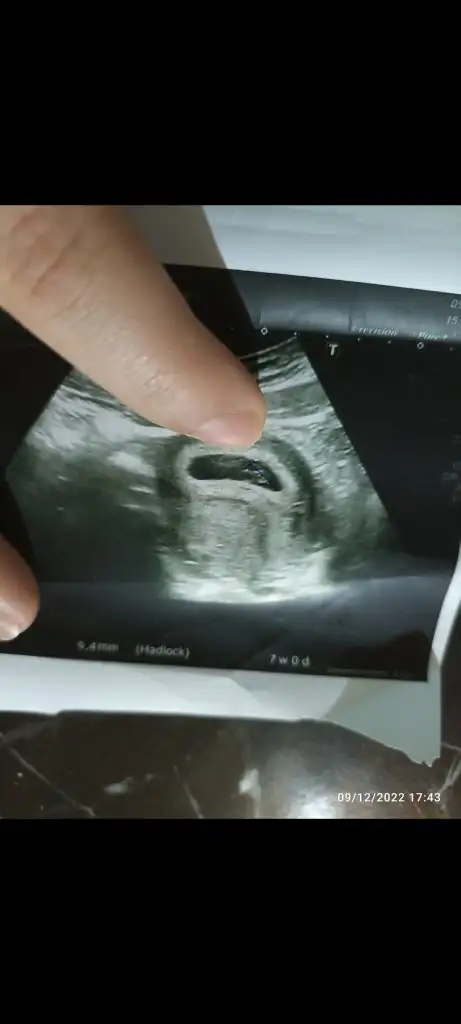

Vajinal ultrason 7 haftalık yorumlar mısın

7 haftalık bir kese sence kızmı erkekmi bilirsen dile benden ne dilersen